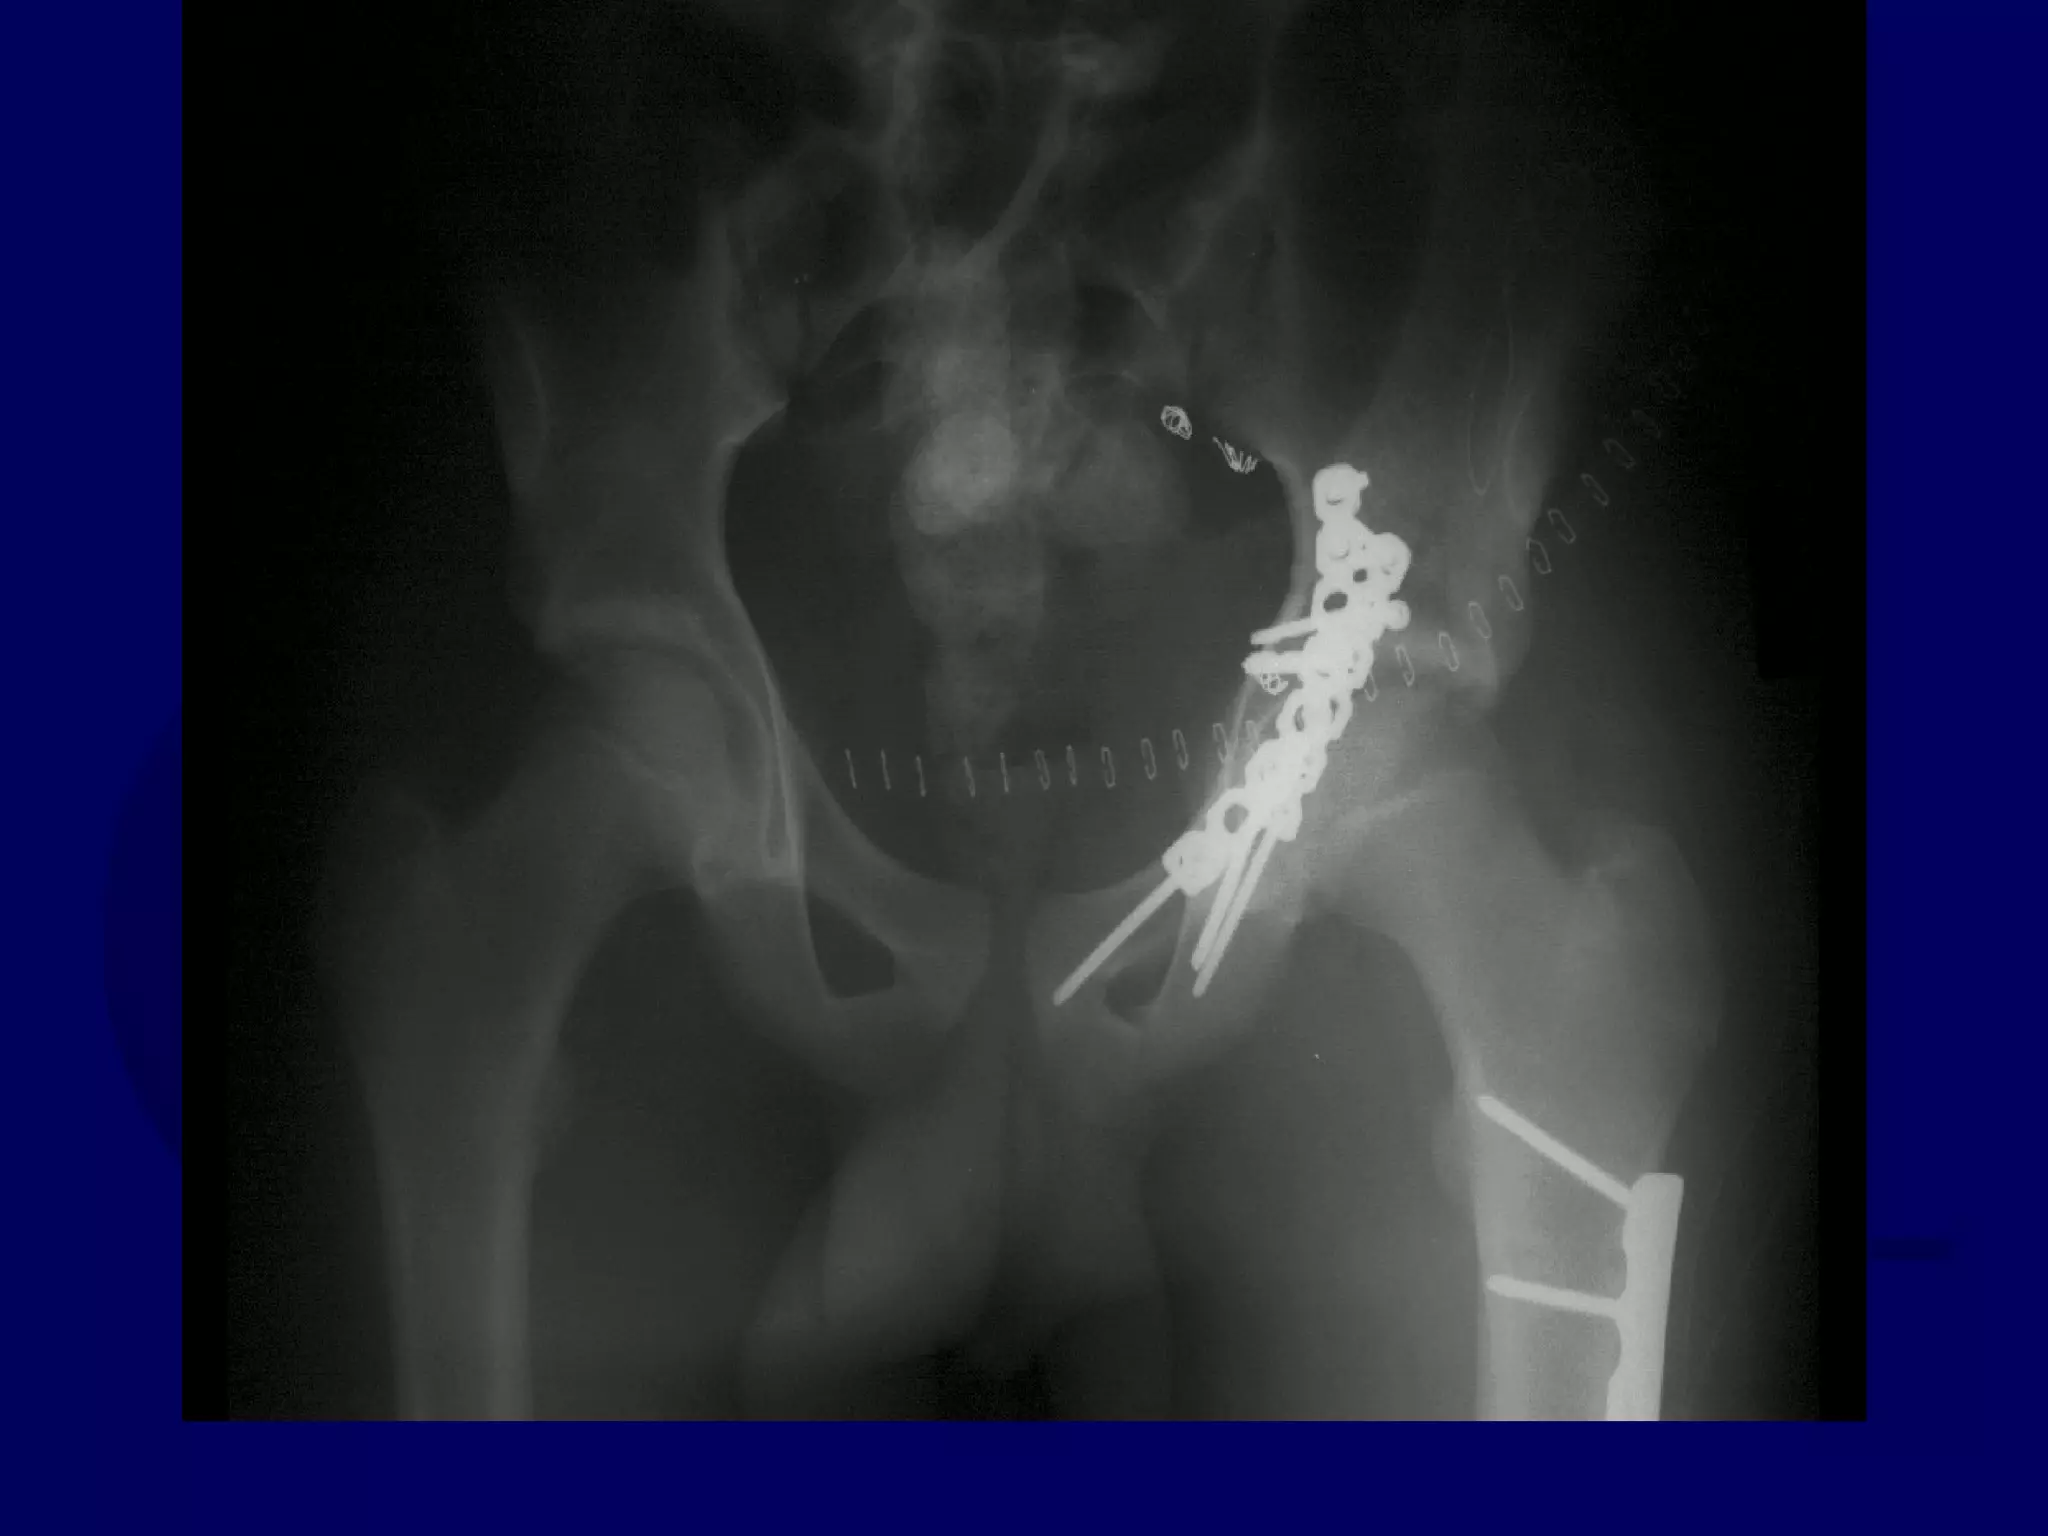

Special Case

“T-Type” Acetabular Fracture

Proximal Femur Fracture

14 y.o. Male

Sequential K-L / Ilioinguinal

Initial Kocher-Langenbeck

Approach

P.J. 00.12.18

Subsequent Ilioinguinal

P.J. 00.12.22